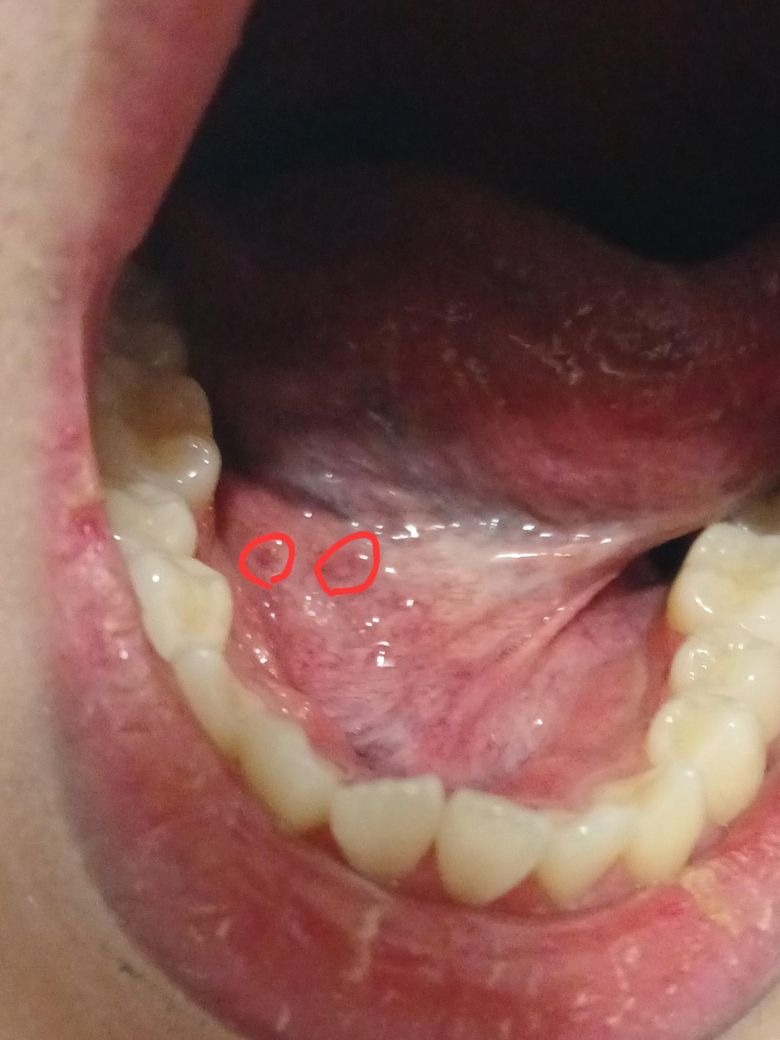

혀 밑에 뭔가 붉은색 혹 같은게 났는데 이게 뭘까요

오늘 저녁식사 이후 혀 밑에 미묘한 이물감을 느껴서 거울을 보고 혀 밑을 비춰봤는데 살짝 하얀 빛깔을 띄며 작은 크기로 올라온 것과 올라오진 않았고 붉은 반점 같은게 하나 보이는데 이게 심각한건지 알 수 있을까요? 병원을 바로 가야할까요?

• 사진상 혀 밑에 보이는 붉은 반점은 위치와 모양으로 보아 침샘관 입구의 일시적 자극, 경미한 점막염, 혹은 음식·치아에 의한 미세 외상 가능성이 높아 보입니다. 혀 밑은 혈관과 침샘이 많이 분포해 있어 자극을 받으면 작은 혹이나 붉은 반점처럼 보일 수 있고, 대개 통증이 심하지 않으며 수일 내 저절로 가라앉는 경우가 많습니다. 현재 설명만으로는 급한 위험 소견은 낮아 보이며 바로 병원을 갈 필요는 없어 보이나, 크기가 커지거나 통증·출혈·단단한 결절 느낌이 생기거나 1~2주 이상 지속되면 이비인후과 또는 치과에서 직접 진찰을 받는 것이 안전합니다. 그 전까지는 만지거나 짜지 말고, 자극적인 음식·흡연을 피하고 구강 위생을 유지하는 정도로 경과를 보시는 것이 안전한 대응입니다.